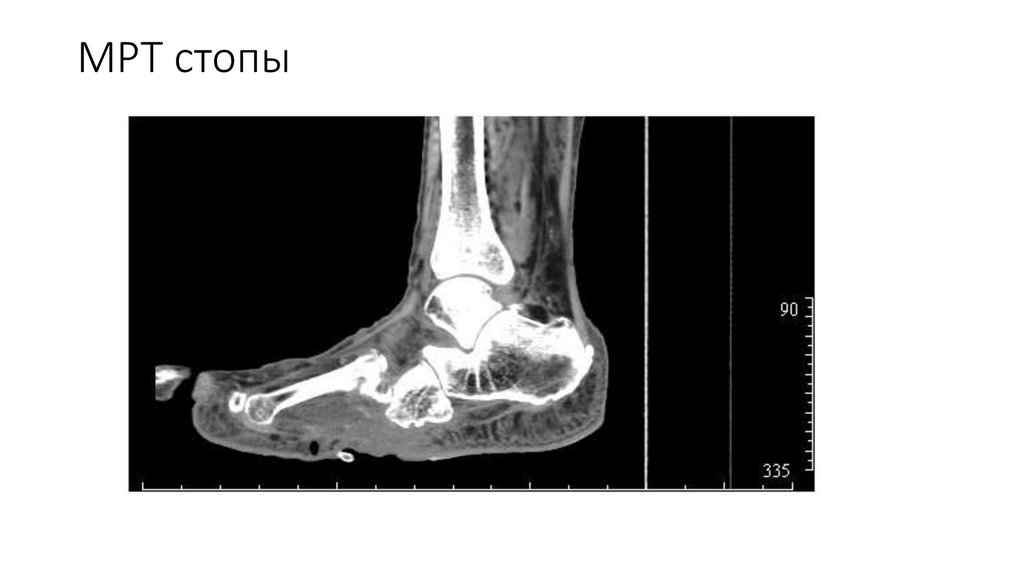

Диагностика

МРТ стопы

56. Диагностика

Стадия ДНОАП

Острая

Хроническая

Клинические

Обязательные

проявления

Проявления диабетической нейропатии

При осмотре

отек и гиперемия

пораженной стопы,

локальная гипертермия

характерная деформация

стопы и/или голеностопного

сустава

Методы

Дополнительные

Инфракрасная

термометрия пораженной

и непораженной

конечности (градиент

температуры >2оС

свидетельствует об острой

стадии ДНОАП)

Рентгенография

пораженного участка

конечности в прямой и

боковой проекциях

(определяется остеопороз,

гиперостозы, вывихи и

подвывихи суставов,

фрагментация костных

структур)

МРТ пораженного

участка конечности

(выявление отека

костного мозга в зоне

пораженного сустава)

МСКТ пораженного

57.

58. МРТ стопы